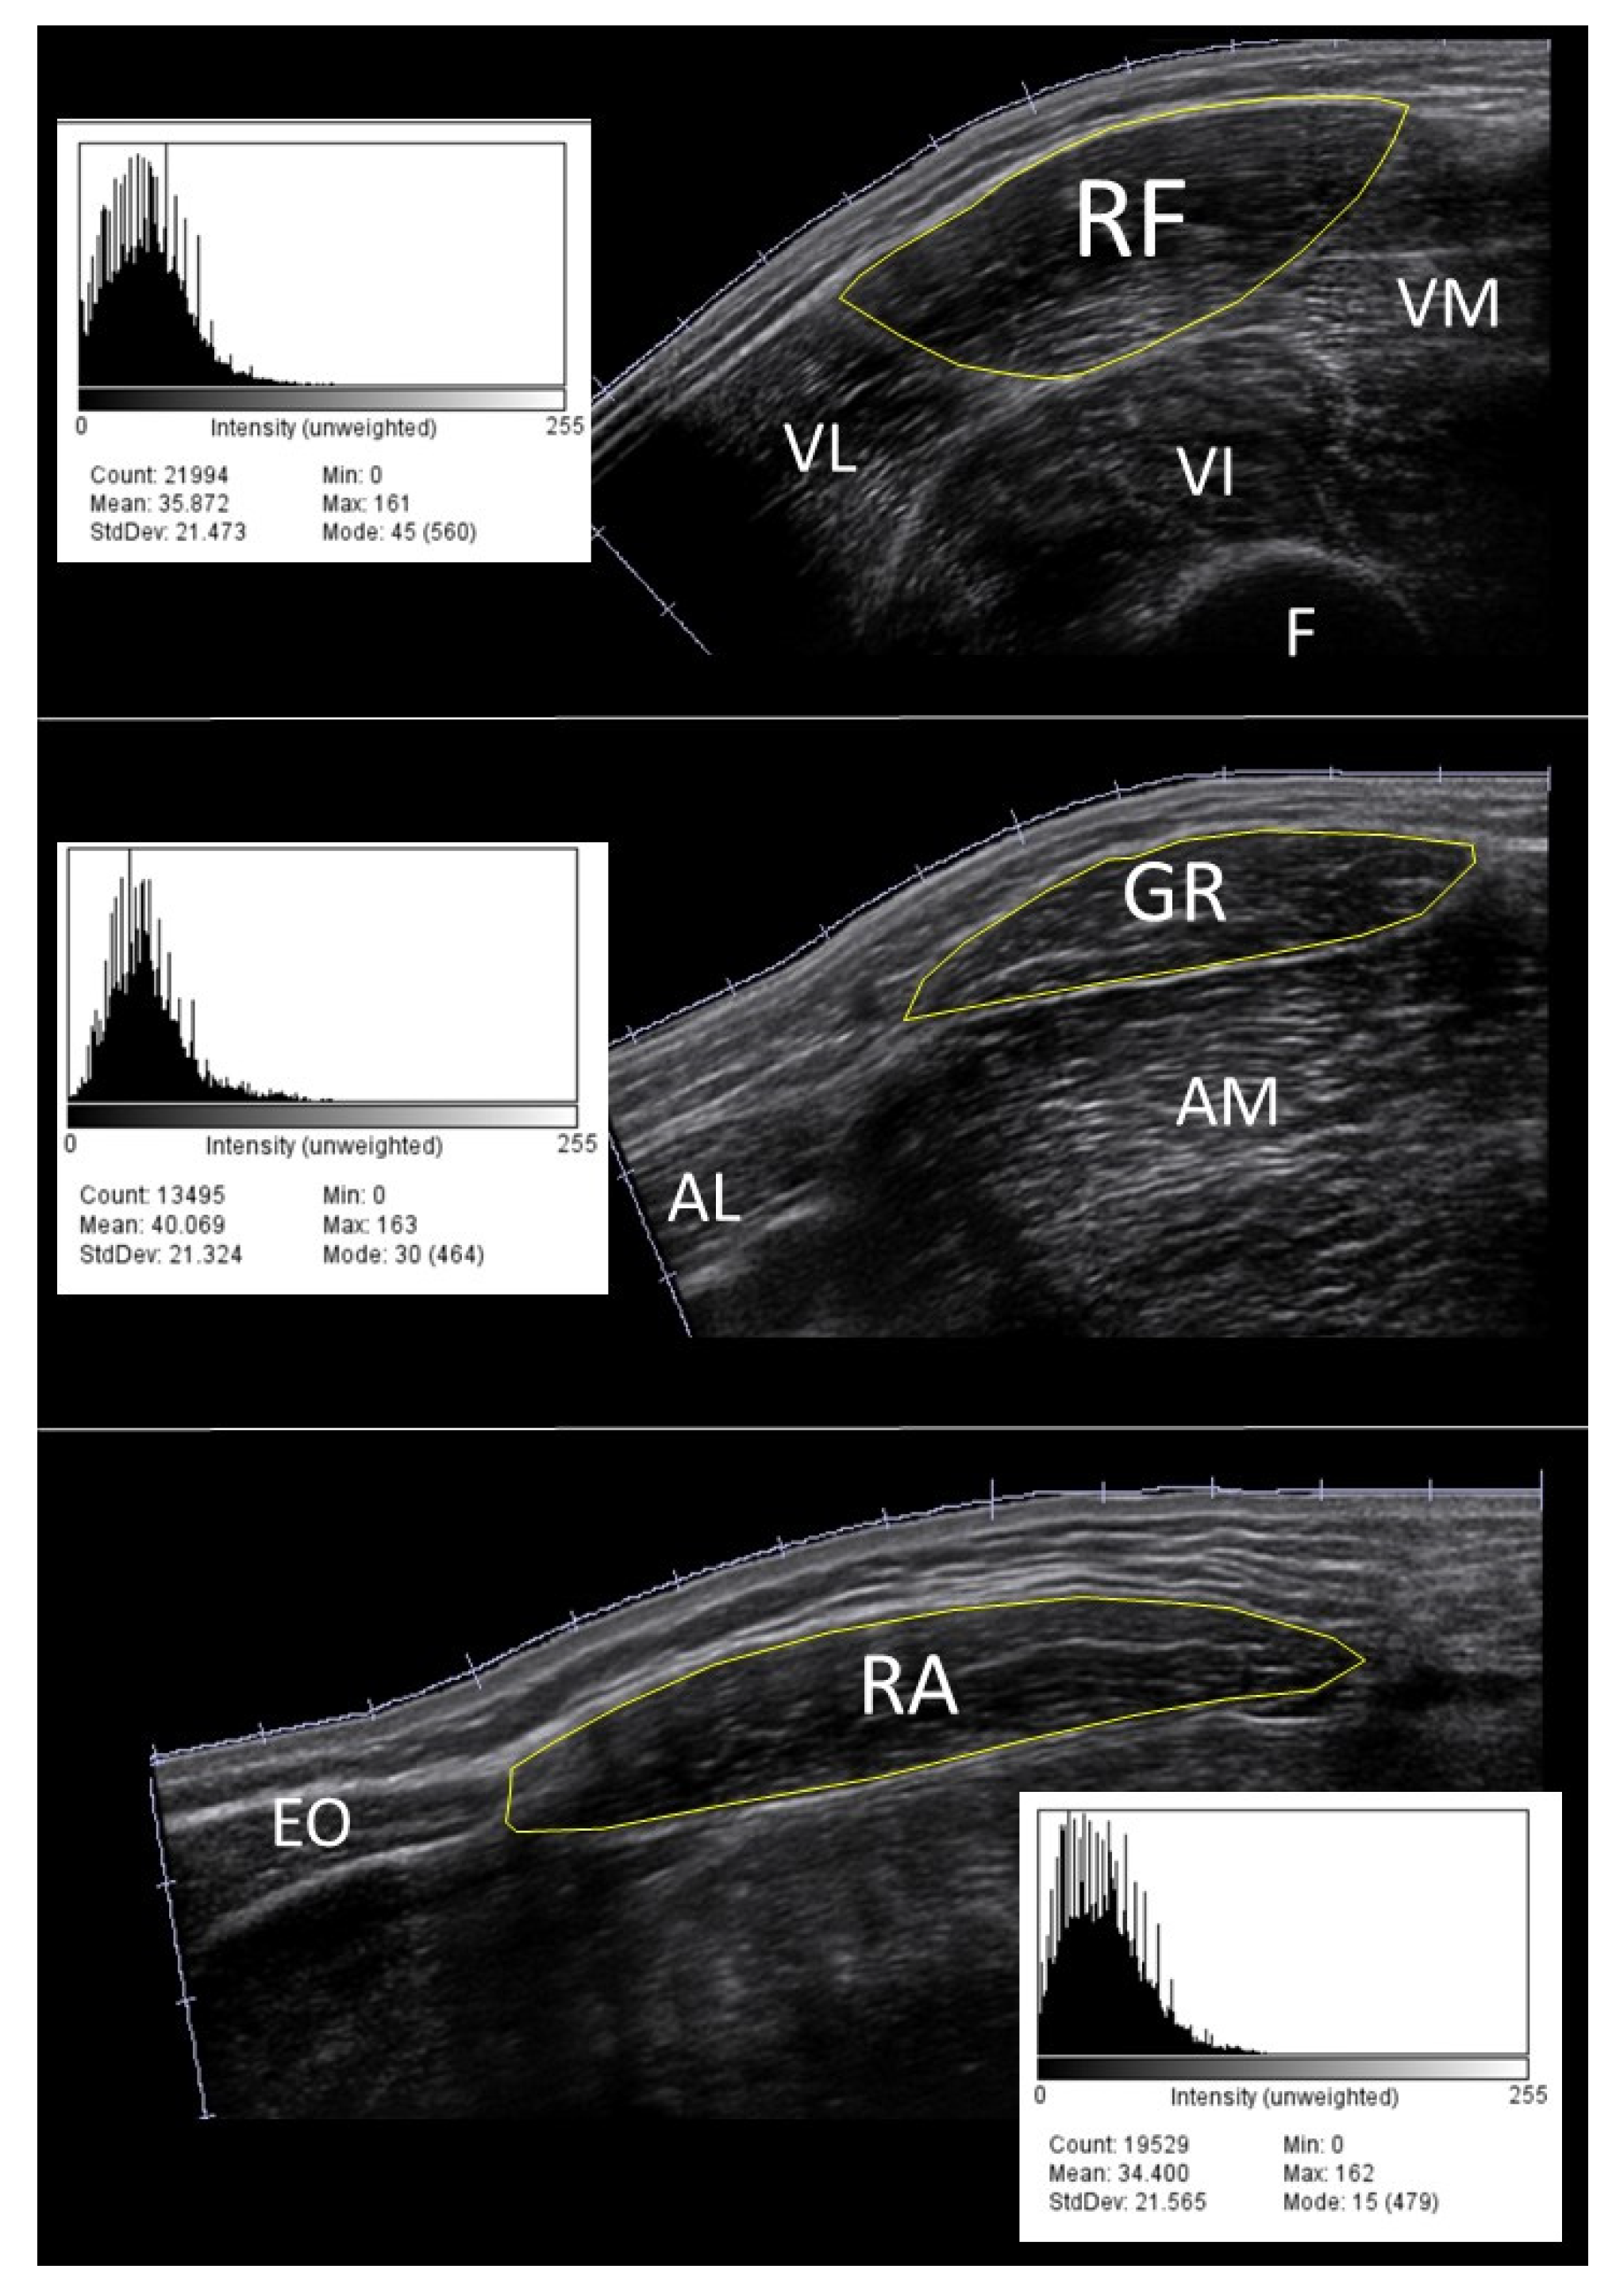

2.2. Scanning Procedure and Image Analysis

3.1. Rectus Femoris Muscle

3.2. Gracilis Muscle

3.3. Rectus Abdominis Muscle